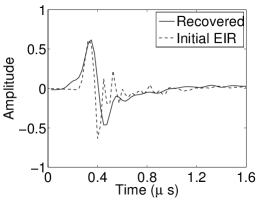

The reconstruction region ( mm2) was represented by pixels with pixel size mm in each dimension. The initial guess of the EIR employed in the VP algorithm was different than the EIR that was assumed when generating the simulated data. This served to simulate a situation in which an experimentally measured EIR contained errors.

Each element in a real-world transducer array possesses its own EIR. In practice, the differences between the EIRs are sometimes neglected and an EIR corresponding to a single element may be used to represent all elements in the array. In some of the studies below, the EIR employed to initialize the VP algorithm (EIR-2 in Figure 1(b)) and the EIR employed to produce the simulated measurements (EIR-1 in Figure 1(b)) were experimentally measured from two different transducer elements in a circular transducer array (see Sec. VI-B). EIR-1 was measured by temporally integrating the PA signal produced by a point source positioned at the focus of the transducer. EIR-2 was measured by use of the method reported in [RNR2011]. In order to investigate the sensitivity of the VP algorithm to the initialization of the EIR, we employed different EIRs obtained by degrading EIR-1 as described later. When solving the sub-problem in Line-2 of Algorithm 1, was initialized as the zero vector. Algorithm 1 was terminated after 500 iterations, since it was observed that the changes in the reconstructed images with more iterations were negligible. When implemented by use of a single core of an Intel Xeon E5-2640 CPU, each iteration required approximately 7s to complete.

Figure 2(a) shows the image reconstructed by use of the conventional iterative method that utilized a system matrix based on EIR-2. Different values of the regularization parameter from the interval were considered. The reconstructed image with the value of that minimized the RMSE was chosen to represent the best performance of the conventional iterative method. Figure 2(a) and the profile in Figure 2(c) demonstrate that the use of an inaccurate EIR can result in strong artifacts and distortions in images reconstructed by use of the conventional methods.

When the VP algorithm was applied, different values of the regularization parameter from the interval and from the interval were considered. The image that minimized the RMSE was chosen and displayed in Figure 2(b). As revealed by this image and the profiles in 2(c), the VP algorithm yielded an image with fewer artifacts and distortions, and image fidelity was improved as reflected by the reduced RMSE.

Figure 7(a) reveals that use of the inaccurate EIR in the conventional iterative method created strong artifacts and distortions. Figures 7(b) confirms that the artifacts and distortions were significantly mitigated when the VP method was employed. Image profiles for both cases are shown in Figures 7(c). The overall accuracy of the recovered EIR, shown in Figure 7(d) and 7(e), was improved, but it contained spurious oscillations.